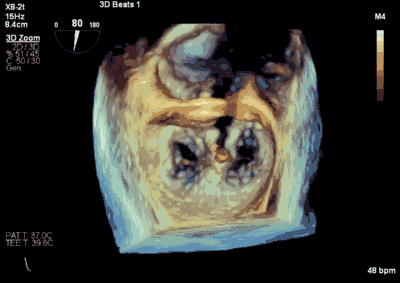

患者全麻以后,在经食道超声心动图和X射线引导下,经股静脉入路,将MitraClip瓣膜夹顺利送至二尖瓣前后叶交界中心处,成功捕捉二尖瓣前叶A2和后叶P2,经超声心动图反复确认瓣叶夹持牢固后,测定有效夹持长度10.4mm,评估反流量降至轻度,释放瓣膜夹,超声心动图评估瓣膜夹位置和功能良好,测定左房压降至26/12mmHg,再次评估反流量仍为轻度,手术顺利完成。

王焱、王斌教授团队通过术前和台北荣民总医院(Taipei Veterans General Hospital)宋思贤教授进行了详细的讨论并制定了最优的手术策略,同时术中视频连线获得宋思贤教授的技术支持,爱情岛论坛 超声内科苏茂龙教授负责术中超声心动图引导。患者全麻以后,在经食道超声心动图和X射线引导下,经股静脉入路,将MitraClip瓣膜夹顺利送至二尖瓣前后叶交界中心处,成功捕捉二尖瓣前叶A2和后叶P2,经超声心动图反复确认瓣叶夹持牢固后,测定有效夹持长度11mm,评估反流量降至微量,释放瓣膜夹,超声心动图评估瓣膜夹位置和功能良好,测定左房压降至11/6mmHg,再次评估反流量仍为微量,手术顺利完成。